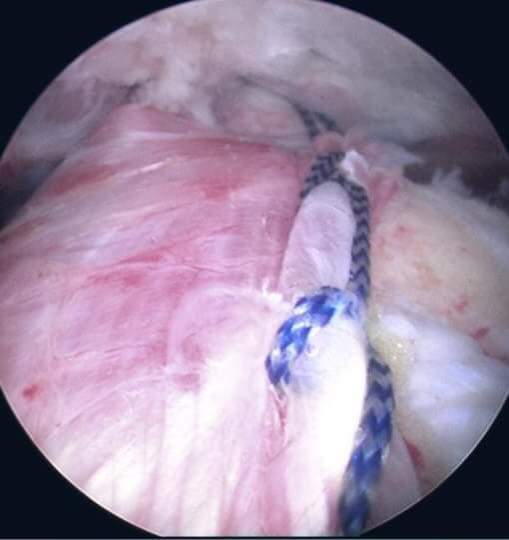

لأول مرة في الأردن ، نقل وتر العضلة الظهرية العريضة بالمنظار في مستشفى الملكة علياء العسكري

الخدمات الطبية الملكية تجري  عملية نقل وتر نوعية  بمساعدة منظار الكتف لأول مرة في الأردن

أجرى فريق جراحة منظار المفاصل والطب الرياضي عملية نقل وتر العضلة الظهرية العريضة بمساعدة المنظار

Arthroscopic-assisted Lattismus Dorsi Tendon Transfer

لمريضة خمسينية في مستشفى الملكة علياء العسكري.

وقال المقدم الطبيب المثنى مصلح اليماني رئيس اختصاص جراحة منظار المفاصل والطب الرياضي أن العملية تجرى لأول مرة في الأردن وتوفر حلولاً للحالات الناتجة عن تمزق العضلات المدورة للكتف في حال استحالة إصلاحها وتأثيرها الكبير على الحركة وخصوصاً قبل ظهور التنكسات المفصلية . كما أشار اليماني إلى تمكن الفريق من القيام بهذا الإجراء الدقيق بالتعاون مع الزملاء من التخصصات الفرعية الأخرى في دائرة جراحة العظام والمفاصل .

وبيّن المقدم الطبيب أحمد المرزوق أخصائي أول جراحة العظام والمفاصل وجراحة عظام أطفال أن الحالة كانت قد تسببت بشلل كاذب "pseudoparalysis" في حركة مفصل الكتف الأيمن نتيجة تمزق أوتار الكتف مع هجرة علوية لعظم العضد وعدم وجود احتكاك داخل المفصل.

ولفت الرائد الطبيب محمد الجزازي أخصائي أول جراحة منظار المفاصل والطب الرياضي أن حالة المريض جيدة، والنتيجة المتوقعة من العملية هي استعادة حركة المفصل بشكل شبه طبيعي بعد علاج فيزيائي ووظيفي يستمر من ٣ إلى ٤ شهور تقريباً.